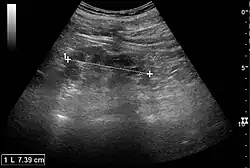

Ultrasound

Kidney ultrasonography is useful for diagnostic and prognostic purposes in chronic kidney disease. Whether the underlying pathologic change is glomerular sclerosis, tubular atrophy, interstitial fibrosis, or inflammation, the result is often increased echogenicity of the cortex. The echogenicity of the kidney should be related to the echogenicity of the liver or the spleen. Moreover, decreased kidney size and cortical thinning are often seen, especially when the disease progresses. However, kidney size correlates to height, and short persons tend to have small kidneys; thus, kidney size as the only parameter is unreliable.[63]